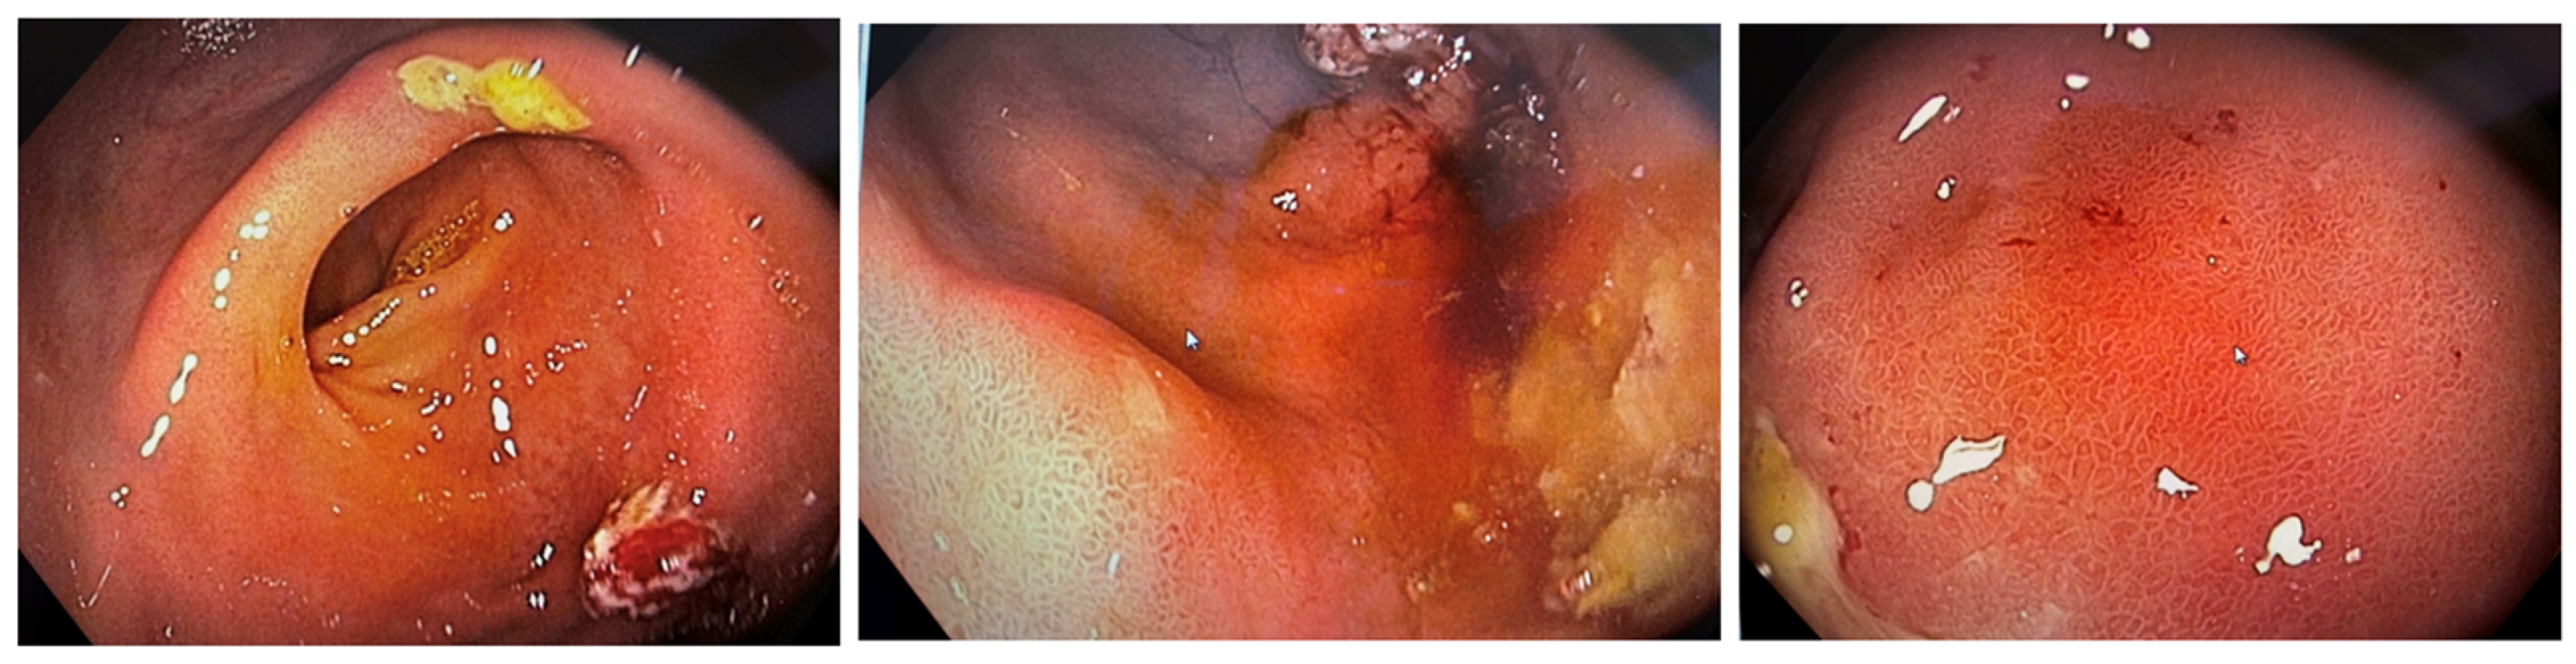

2. Case Presentation